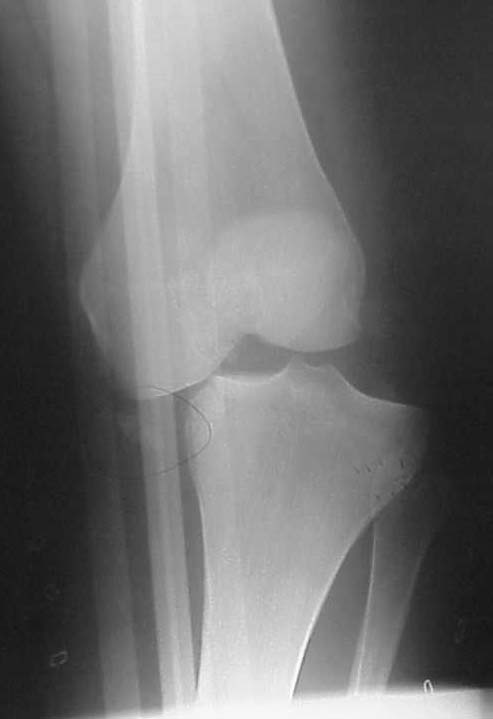

He had STSG and delayed ACL/PCL and posterolateral corner reconstruction at 3 weeks. I only have his injury films, but he says his leg always has appeared to be in varus. He has a sedentary job, painless ROM 0-100 degrees, walks w/ slight limp. He made an appointment to establish a new physician as his insurance has changed. His clinical appearance and current xrays are impressive, but he does not seem too concerned. Any thoughts on interventions? He is getting his post reconstruction xrays for review.

AP 18 mos

Varus

My assessment is that you have a young (23) patient with chronic severe subluxation of the knee joint and deformity 1.5 years after knee dislocation with failed ligamentous repairs of the ACL, PCL and PLC. His motion is surprisingly good (0-100) and his symptoms are surprisingly minimal. He is showing radiographic degeneration of the joint and also has peroneal palsy.